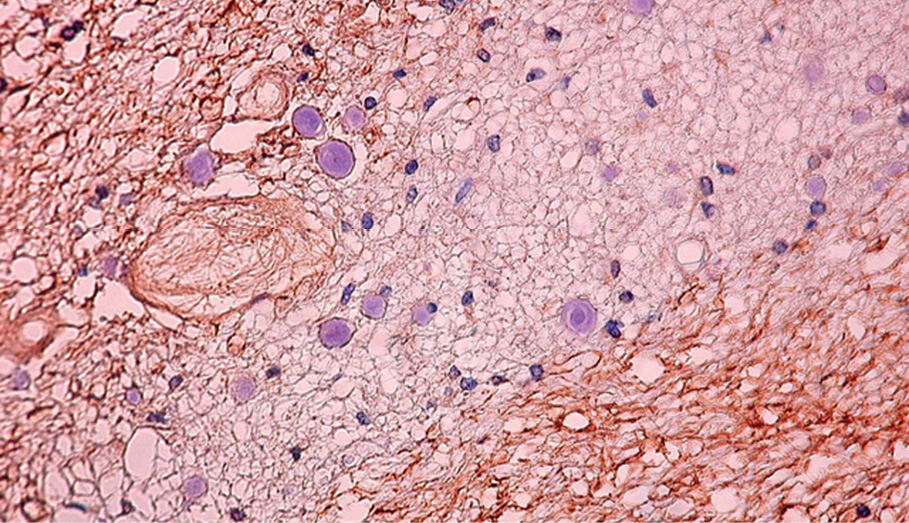

Рисунок 3. Фрагмент коры предцентральной извилины головного мозга женщины 79 лет. Визуализируются микроглиоциты мелкого и среднего диаметров (отмечены стрелками). Экспрессия белка нейрофиламентов в структуре ткани равномерная, сама структура неоднородная, наличие переходных зон. Увеличение 100.

В ткани мозолистого тела возрастные нейродегенеративные изменения выражены более явно. Так, к старческому возрасту в местах скоплений микроглиоцитов отмечается значительное снижение экспрессии нейрофиламентов с формированием участков их разрежения (рисунки 3, 4).

Как известно, нейрофиламенты, являющиеся промежуточными структурами нервных клеток, представляют собой длинные гибкие нитеподобные цитоскелетные полимеры. Их функции разнообразны – от структурной до транспортной [11, 12]. Нами установлено, что в ткани коры предцентральной извилины головного мозга как в первом периоде зрелого возраста, так и в старческом возрасте экспрессия нейрофиламентов равномерная.

Экспрессия нейрофиламентов в ткани коры предцентральной извилины головного мозга как в первом периоде зрелого возраста, так и в старческом возрасте равномерная. Наряду с этим в ткани мозолистого тела общая тенденция возрастной динамики заключается в значительном снижении экспрессии нейрофиламентов в местах скоплений микроглиоцитов и появлением участков их разрежения к старческому возрасту.